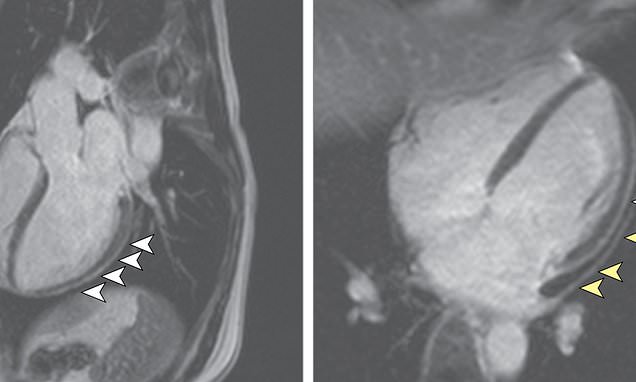

Arrows point out areas of the hearts of coronavirus survivors that became thicker and inflamed after infection. The study found blood markers in these survivors typically only seen after someone sufferers

The researchers could see signs of heart damage in MRIs taken of 78 out of the 100 survivors.

Nearly as many – 76 percent – had high levels of a protein called troponin, comparable to what is seen in a person who has suffered a heart attack.

Sixty of the participants had signs of heart inflammation, even though it had been 71 days, on average, since they’d been diagnosed with coronavirus.